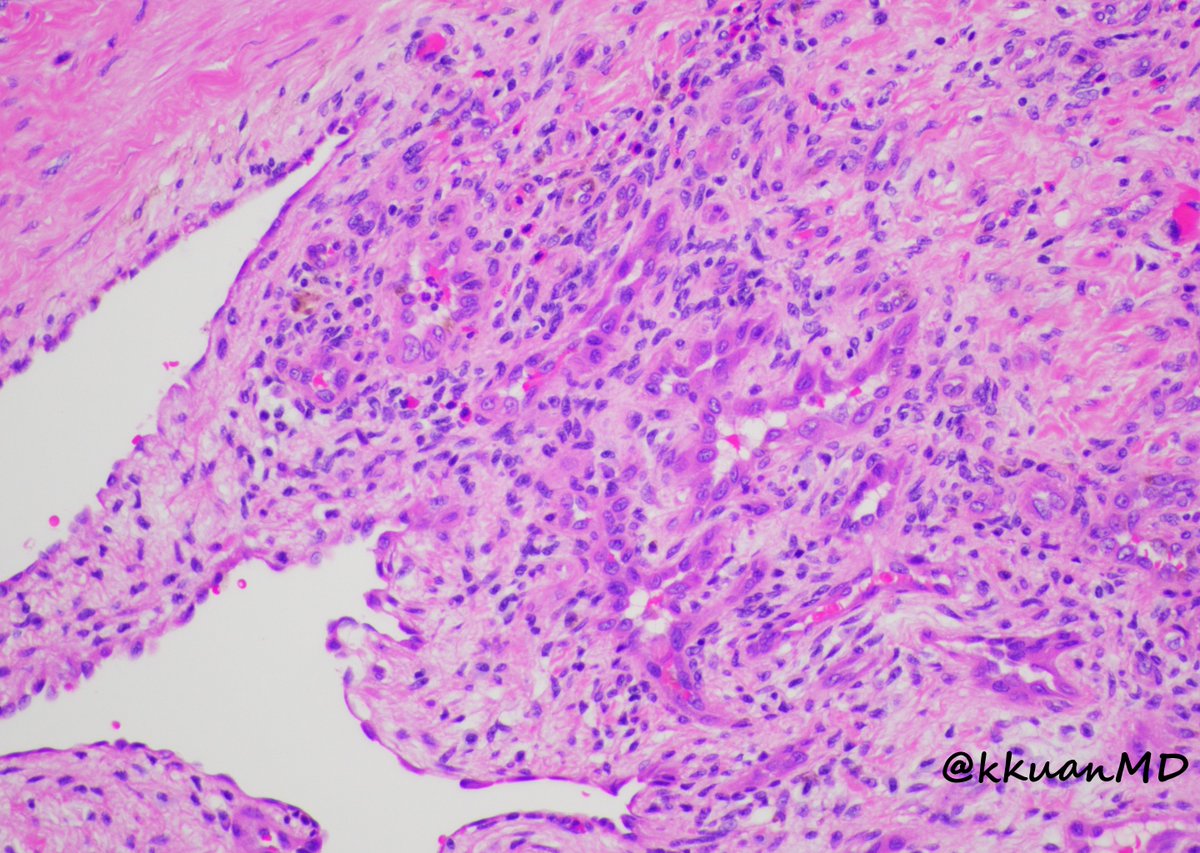

24yo F, 2cm wrist lesion. #pathology #pathtwitter #BSTpath #pathboards Einstein Montefiore Pathology @histiocytosisX Jason L. Hornick, M.D., Ph.D. Tristan Rutland MBBS FRCPA IFCAP Brian Cox, MD, MAS Vish Killari MD MPH Celina Stayerman MD Adam L. Booth, MD Jerad Gardner, MD Olaleke Folaranmi